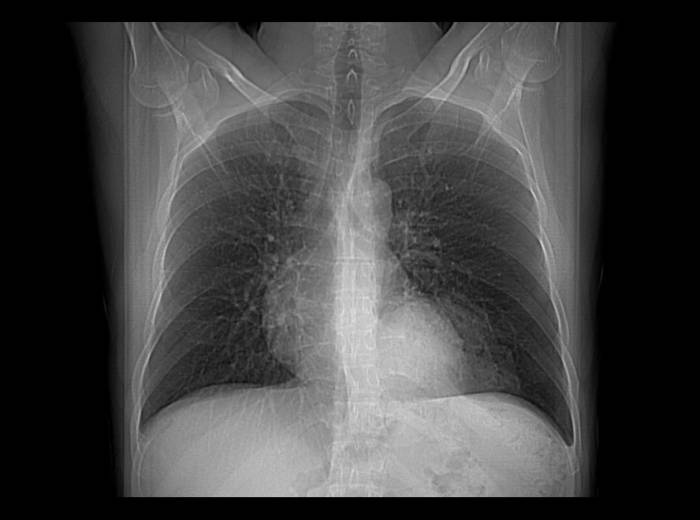

- Рентгенологическое исследование позволяет увидеть расположение органов, для этого предварительно пациент выпивает контрастное вещество;

Диафрагмальные грыжи отличаются от других форм выпячивания отсутствием внешнего дефекта, так как часть желудка или кишки выходят не под кожу, в другую полоть. Признаки диафрагмального выпячивания проявляются в виде нарушения работы пищеварительной системы, потому только рентгенологическая диагностика позволяет увидеть реальное заболевание пищеводно-диафрагмальной связки.

В случае небольшого размера дефекта признаки выпячивания желудка могут вовсе отсутствовать, и только рентгенологическая диагностика при обследовании больного может указать на наличие заболевания.